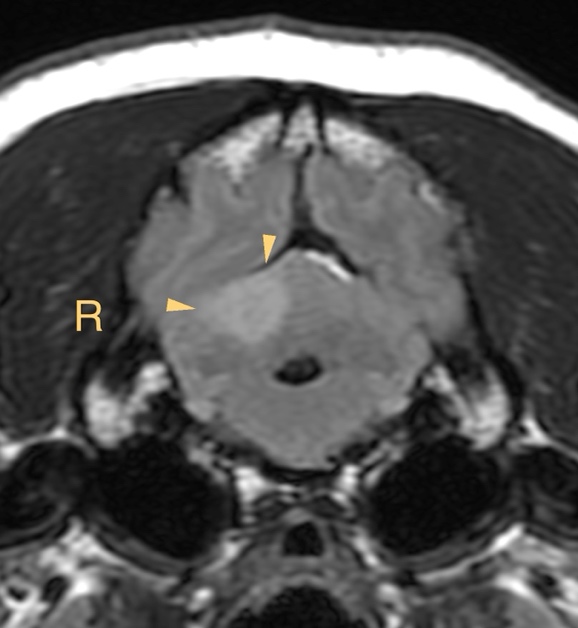

MRI所見

小脳右前小脳動脈領域にT2WI/FLAIR:高信号、DWI:高信号、ADC:一部低信号(部分的な拡散抑制を示唆)

→急性期小脳梗塞を強く疑う所見

この症例もやっぱり小脳中位核を含んでいます、瞳孔不同(右眼散瞳)があったに違いない!!

【MR画像】横断像 FLAIR画像

【MR画像】横断像 FLAIR画像